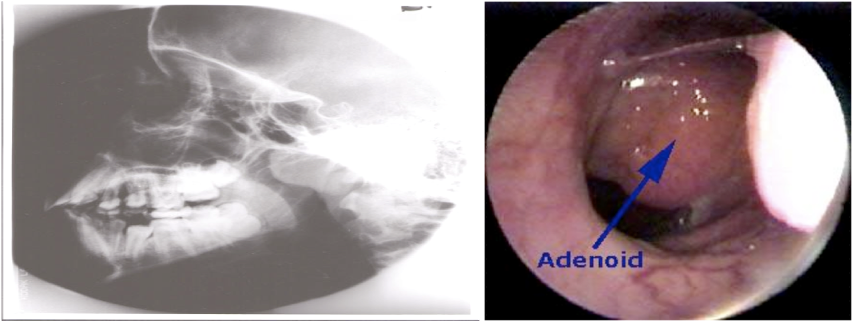

- Lymphoid hyperplasia.